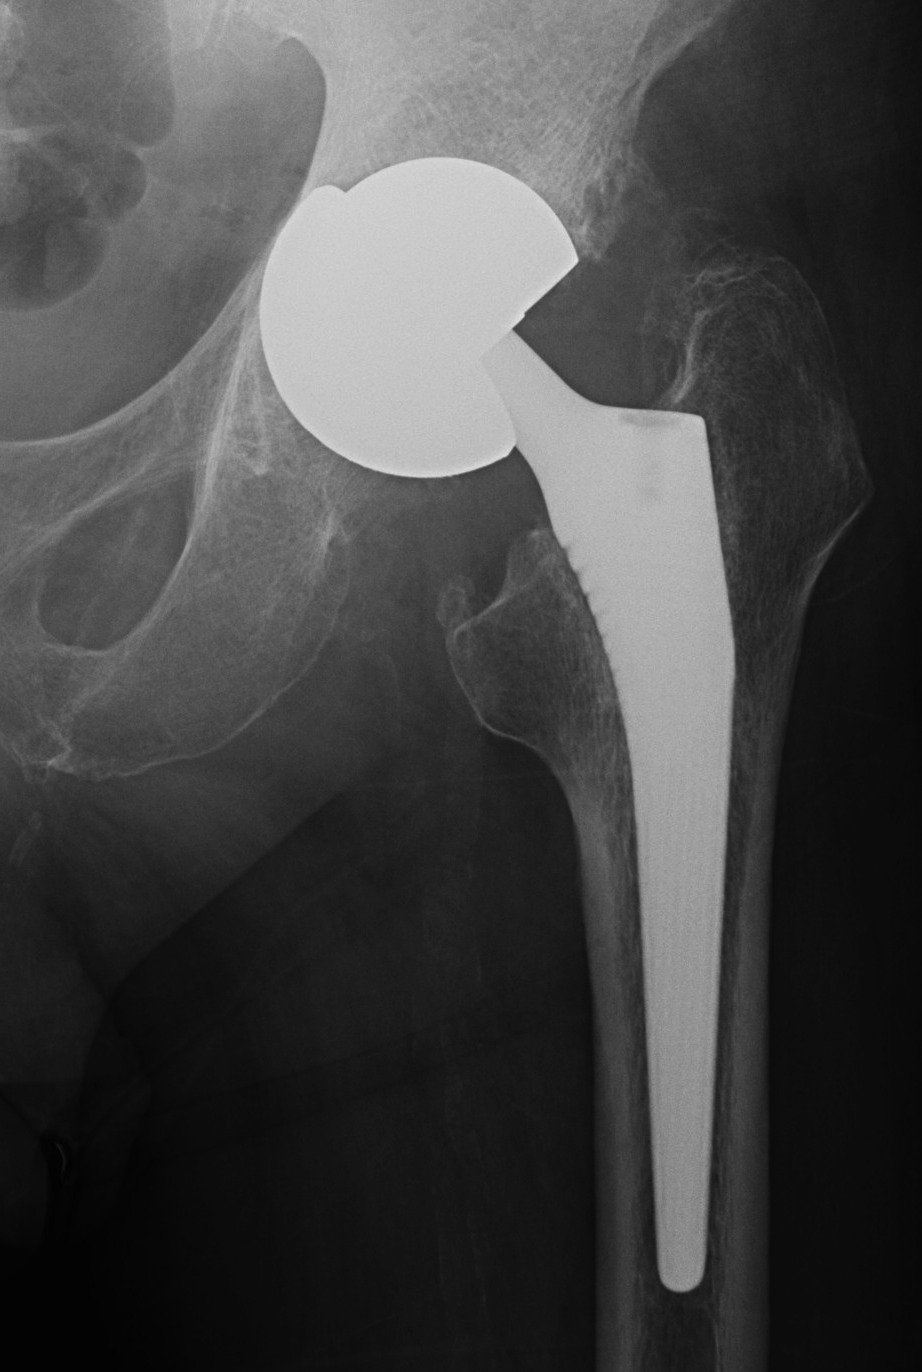

Cup Design

Stryker Trident Titanium and HA coated

Zimmer Trabecular Metal Tantalum Cup

Material

- titanium - similar modulus of elasticity to bone, most common

- tantalum - ? superior osteointegration, used often in revision

Shape

- designed to engage in the outer periphery of acetabulum

- hemispherical / nonhemispherical / elliptical